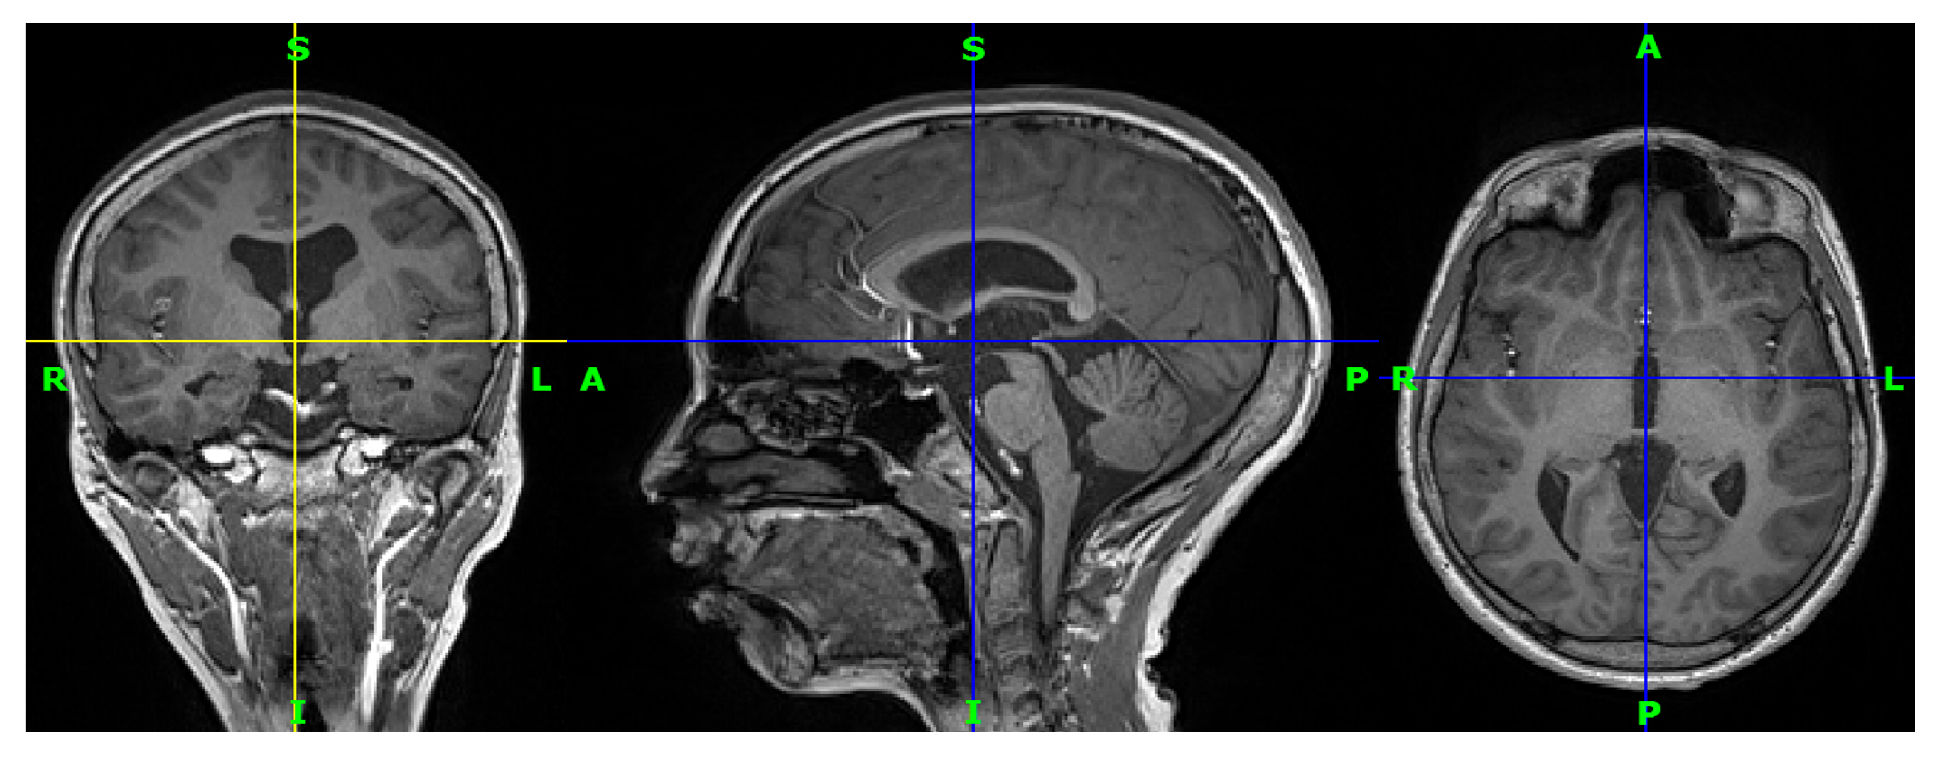

3.1. Data Acquisition

3.2. Preprocessing